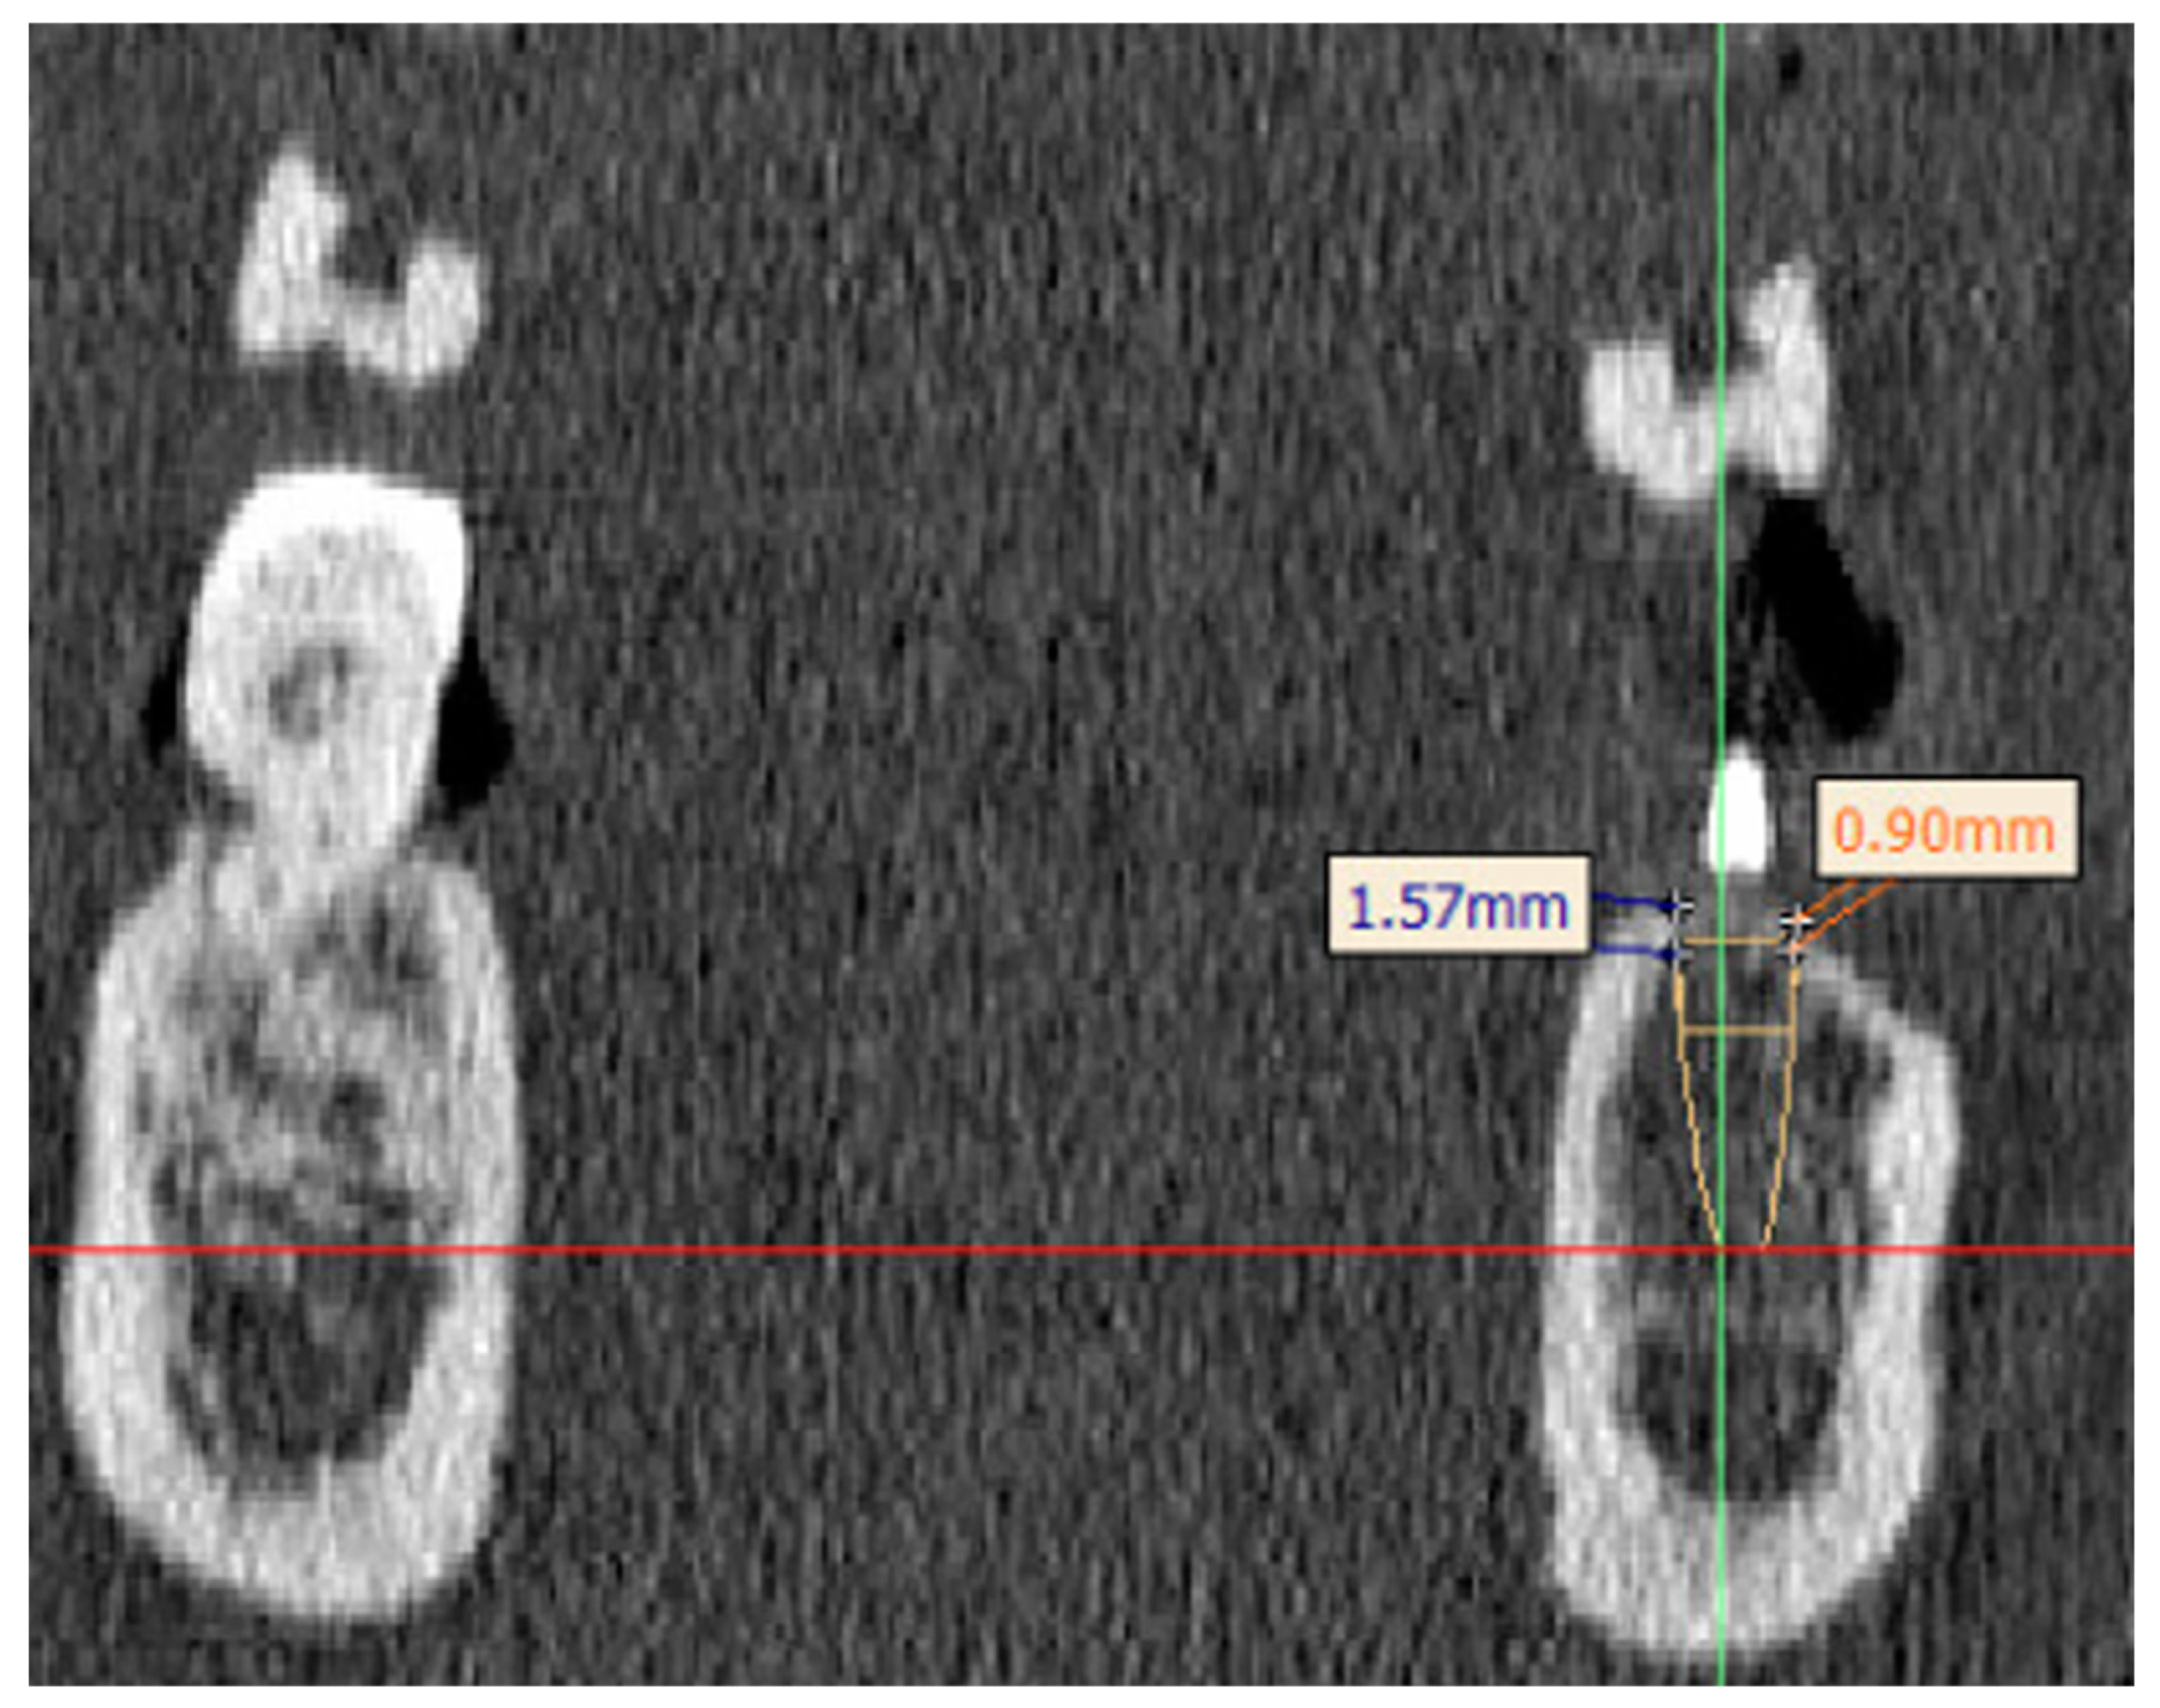

2.4. Image Analysis and Segmentation

2.6. Segmentation